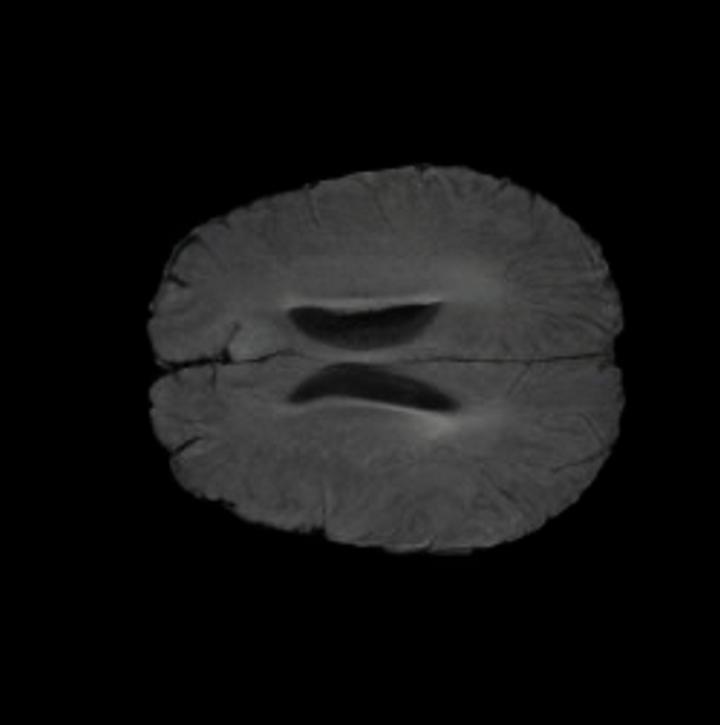

Brain Volumes Preservation. The generated MRIs by our X-Diffusion retain almost the exact same average brain volume vs of the real MRIs.

B.2 Brain Volumes Preservation

The comparison of generated MRIs versus reference MRIs suggests a nearly perfect preservation of brain volume (in mm3) with median volume of reference MRIs of versus generated MRIs (see an example of brain generation in Figure 11).